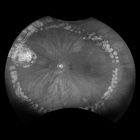

MonacoPro provides an exciting new way to enhance your clinical exam. The only ultra-widefield retinal imaging device with integrated Spectral Domain OCT, MonacoPro produces a 200° single shot optomap image in less than ½ second and also provides cross-sectional 40° OCT views of retinal structures. Engineered for efficiency, MonacoPro captures up to five imaging modalities for both eyes in just 90 seconds, optimising workflow, streamlining diagnostics, and delivering superior patient care.

optomap Image Modalities

- colour rg

- Sensory Retina

- Choroidal

- green af

- SD-OCT

- 3-in-1 Color DepthTM Imaging provides important clinical data from the retinal surface, through the choroid